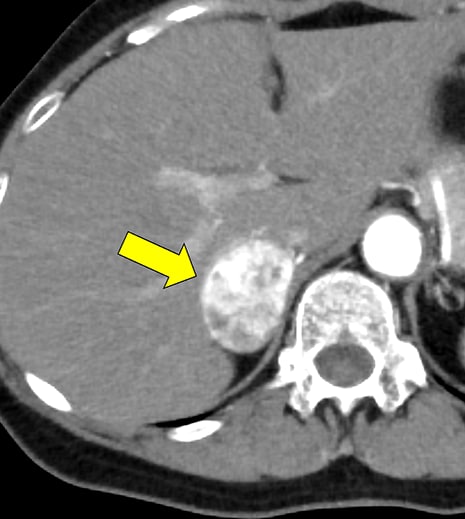

褐色細胞腫は副腎髄質に存在するクロム親和性細胞に由来する腫瘍で、カテコールアミンなど種々の生理活性物質を産生する。ダイナミック造影で動脈相での強い濃染と持続する造影効果が特徴とされ、サイズが大きい病変は嚢胞変性や出血、壊死を伴うことが多い。かつては、臨床的に褐色細胞腫が疑われる場合、ヨード造影剤の投与はカテコールアミンの過剰放出を誘発し、高血圧クリーゼを引き起こす可能性があるため原則禁忌とされていた。しかし、現在汎用されている非イオン性・低浸透圧性造影剤であればこの現象は起こらないとの報告もあり、European Society of Urogenital Radiology Guidelines on Contrast Media, ver 10.0では、「経静脈的ヨード造影剤の投与をする場合でも特別な準備の必要はない」と記載されている。イオプロミドの電子添文上は、禁忌にはなっていないものの、「慎重に投与すること」との記載になっている。本例では、血管腫疑いとして合計5回の造影CTが行われているが、血圧変動や頭痛、動悸などの症状は一度も認められなかった。

本例の画像所見として、褐色細胞腫としてダイナミック造影の濃染パターンは典型的ともいえたが、大きさの割に変性が乏しい点、MIBGシンチでの核種集積に乏しい点、ホルモン産生に乏しい点など非典型的な要素が複数存在し、海綿状血管腫を除外しきれなかった。なお、褐色細胞腫はRET遺伝子変異による多発性内分泌腺腫症(multiple endocrine neoplasia;MEN)type 2A・2B、VHL遺伝子によるvon Hippel-Lindau病、NF1遺伝子による神経線維腫症1型に生じることが知られているが、これらの疾患を想起させるような他病変は本例には見つかっていない。

腺腫や骨髄脂肪腫など良性と断定できない副腎腫瘍の鑑別をする際、大きい病変であれば褐色細胞腫や副腎癌、悪性リンパ腫などが考慮される。核医学検査も有用ではあるが、本例のように偽陰性となることも稀にあり、その際はダイナミック造影パターン、血管への浸潤、転移の有無などから判断しなければならない。適切なタイミングで撮像されたダイナミック造影CTは、多血性病変であるかの評価、周囲の血管との関係性、多血性の転移巣の有無などの判断に寄与し、診断の重要な手がかりとなると考える。